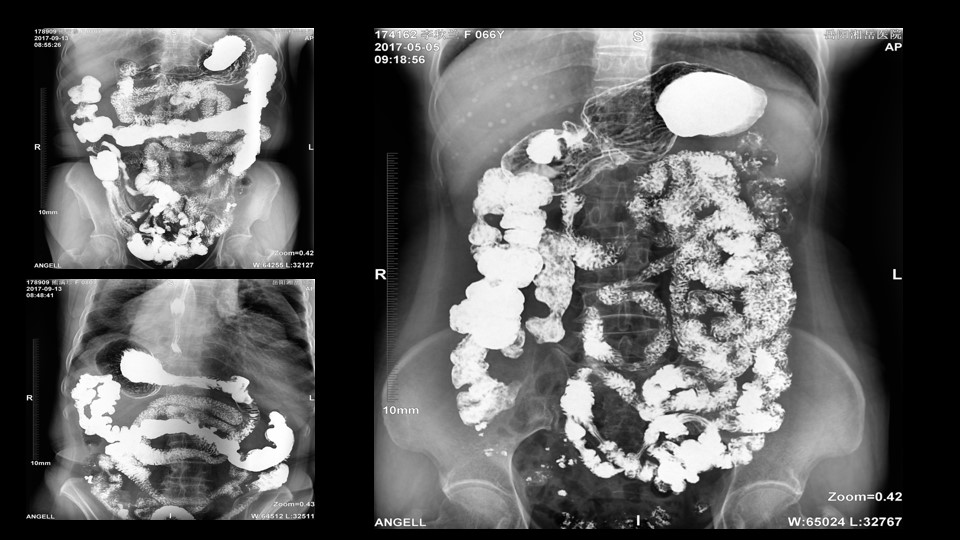

会议开始,岳阳市医学会放射分会副主委、湘岳医院放射科蔡雨主任,结合自身在放射影像的20多年经验,为参会嘉宾分享了动态DR在消化道造影中的应用价值。作为动态DR用户,蔡雨主任结合动态DR的实际拍片与操控经验,分享了动态DR技术在相关群体疾病检查上的独到优势和人文关怀。蔡雨主任说到:“随着内镜技术的发展以及CT、MR的发展,消化道造影在减少,但是这并不意味着消化道造影的价值在下降。以老年人为例,很多老年群体都患有严重的心肺疾病、或者消化道畸形,很多老年人本身就有糖尿病、高血压等等综合疾病,传统内镜的检查对于这类群体来说是一件难以忍受的痛苦,而动态DR的多项创新技术让这类群体的消化系统疾病筛查变得更为人性和精准。任何一个好的消化道造影,一定是患者、诊断医生、临床医生三方满意的结果。ty8天游平台登录科技动态DR技术利用900万像素高清拍片、大幅面透视、高清点片、视频保存与回放等核心功能,完全满足临床对消化道气钡双重造影检查的需要。图像质量全面超越以往模拟胃肠机、影增数字胃肠机”。蔡雨主任全面演示了动态DR在食道造影、上消化道造影、小肠双对比造影、结肠气钡双对比造影中的应用,通过动态DR可以清晰获得临床诊断和评估的图像依据。

▲蔡雨主任使用动态造影图像示例